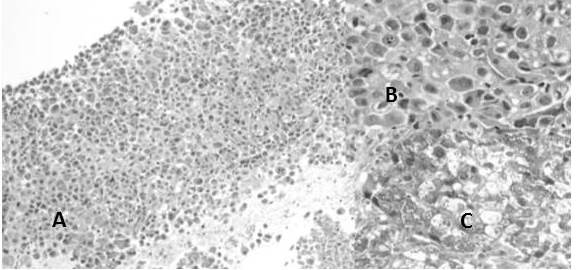

Por otro lado se reclasificaron 50 casos de carcinoma de CCE: encontrando que el CCE poco diferenciado no queratinizante representó el 40 % de los casos (Figura 11), el CCE bien diferenciado queratinizante resultó el 36 % (Figura 12), el CCE moderadamente diferenciado queratinizante representó el 20 % (Figura 13) y finalmente el CCE basaloide (Figura 14) fue el 4 % (Cuadro 7)

En el estudio los casos de carcinomas neuroendocrinos estuvieron representados en su mayoría por carcinomas neuroendocrinos de células pequeñas con 80 % de los casos (Figura 13), los carcinomas de células grandes (Figura 14) fueron 13,3 % y se observó un caso 6,7 % de tumor carcinoide típico (Figura 14) (Cuadro 10).